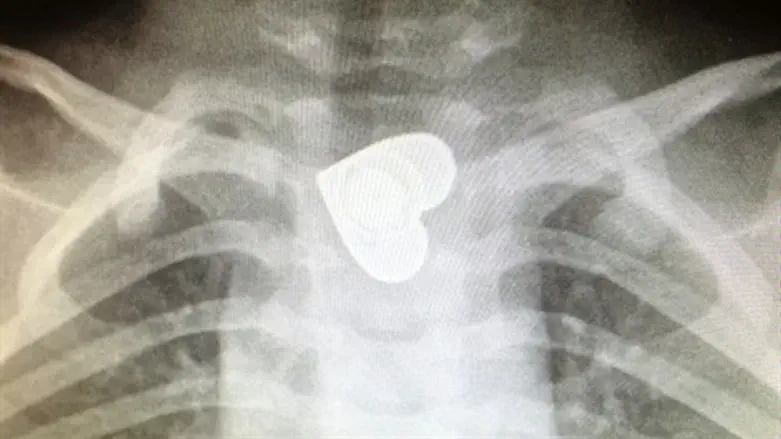

במסגרת בירור רופא הילדים, נשלח הילד לצילום צוואר, אשר הראה כי הילד בלע כפתור בגודל של כ-2.5 על 2.5 ס"מ, כמעט כמו גודלו של מטבע מחצית השקל. אולם, מה שהפתיע יותר את הרופאים הייתה צורתו של הכפתור אשר נראתה בבירור בצילום הרנטגן: בחלקו התחתון של הוושט של הילד, נח לו העצם הזר שצורתו כצורת לב.

"בשל גודלו של הכפתור, הוא חסם את הוושט של הילד וזו הסיבה שהוא לא הצליח לשתות או לאכול", מסבירה ד"ר שורוק נערה, מתמחה במחלקת אא"ג ברמב"ם, אשר הייתה כוננית בזמן האירוע, "לשמחתנו הרבה הכפתור לא חסם את הנשימה והילד לא היה במצוקה, אך מיקומו של הכפתור יכול להוביל לסיבוכים והחלטנו להכניס אותו לטיפול חירום".